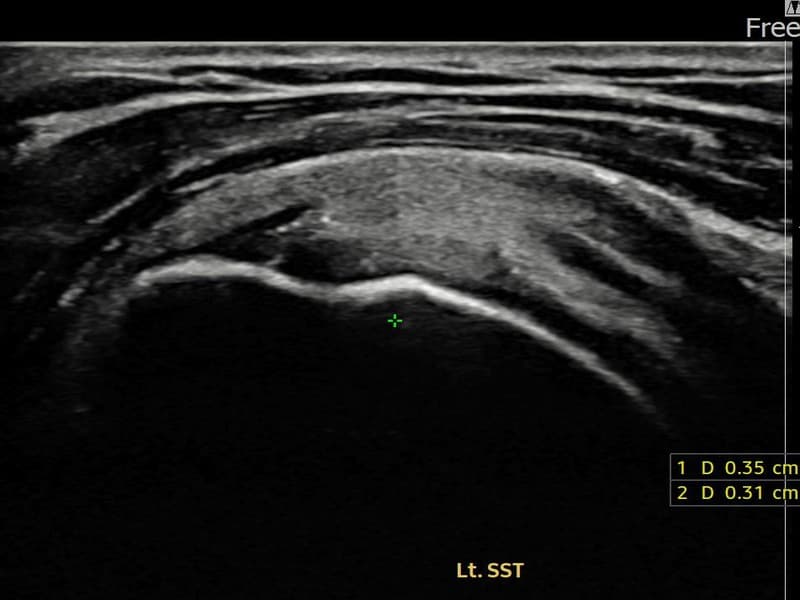

术前

术前超声确认左侧 冈上肌腱 附着部部分撕裂,左侧冈上肌腱回声不连续伴肌腱缺损(5mm × 3mm (肌腱厚度约25%缺损))。术后超声显示撕裂部位充满再生组织,肌腱连续性恢复,回声模式正常化。